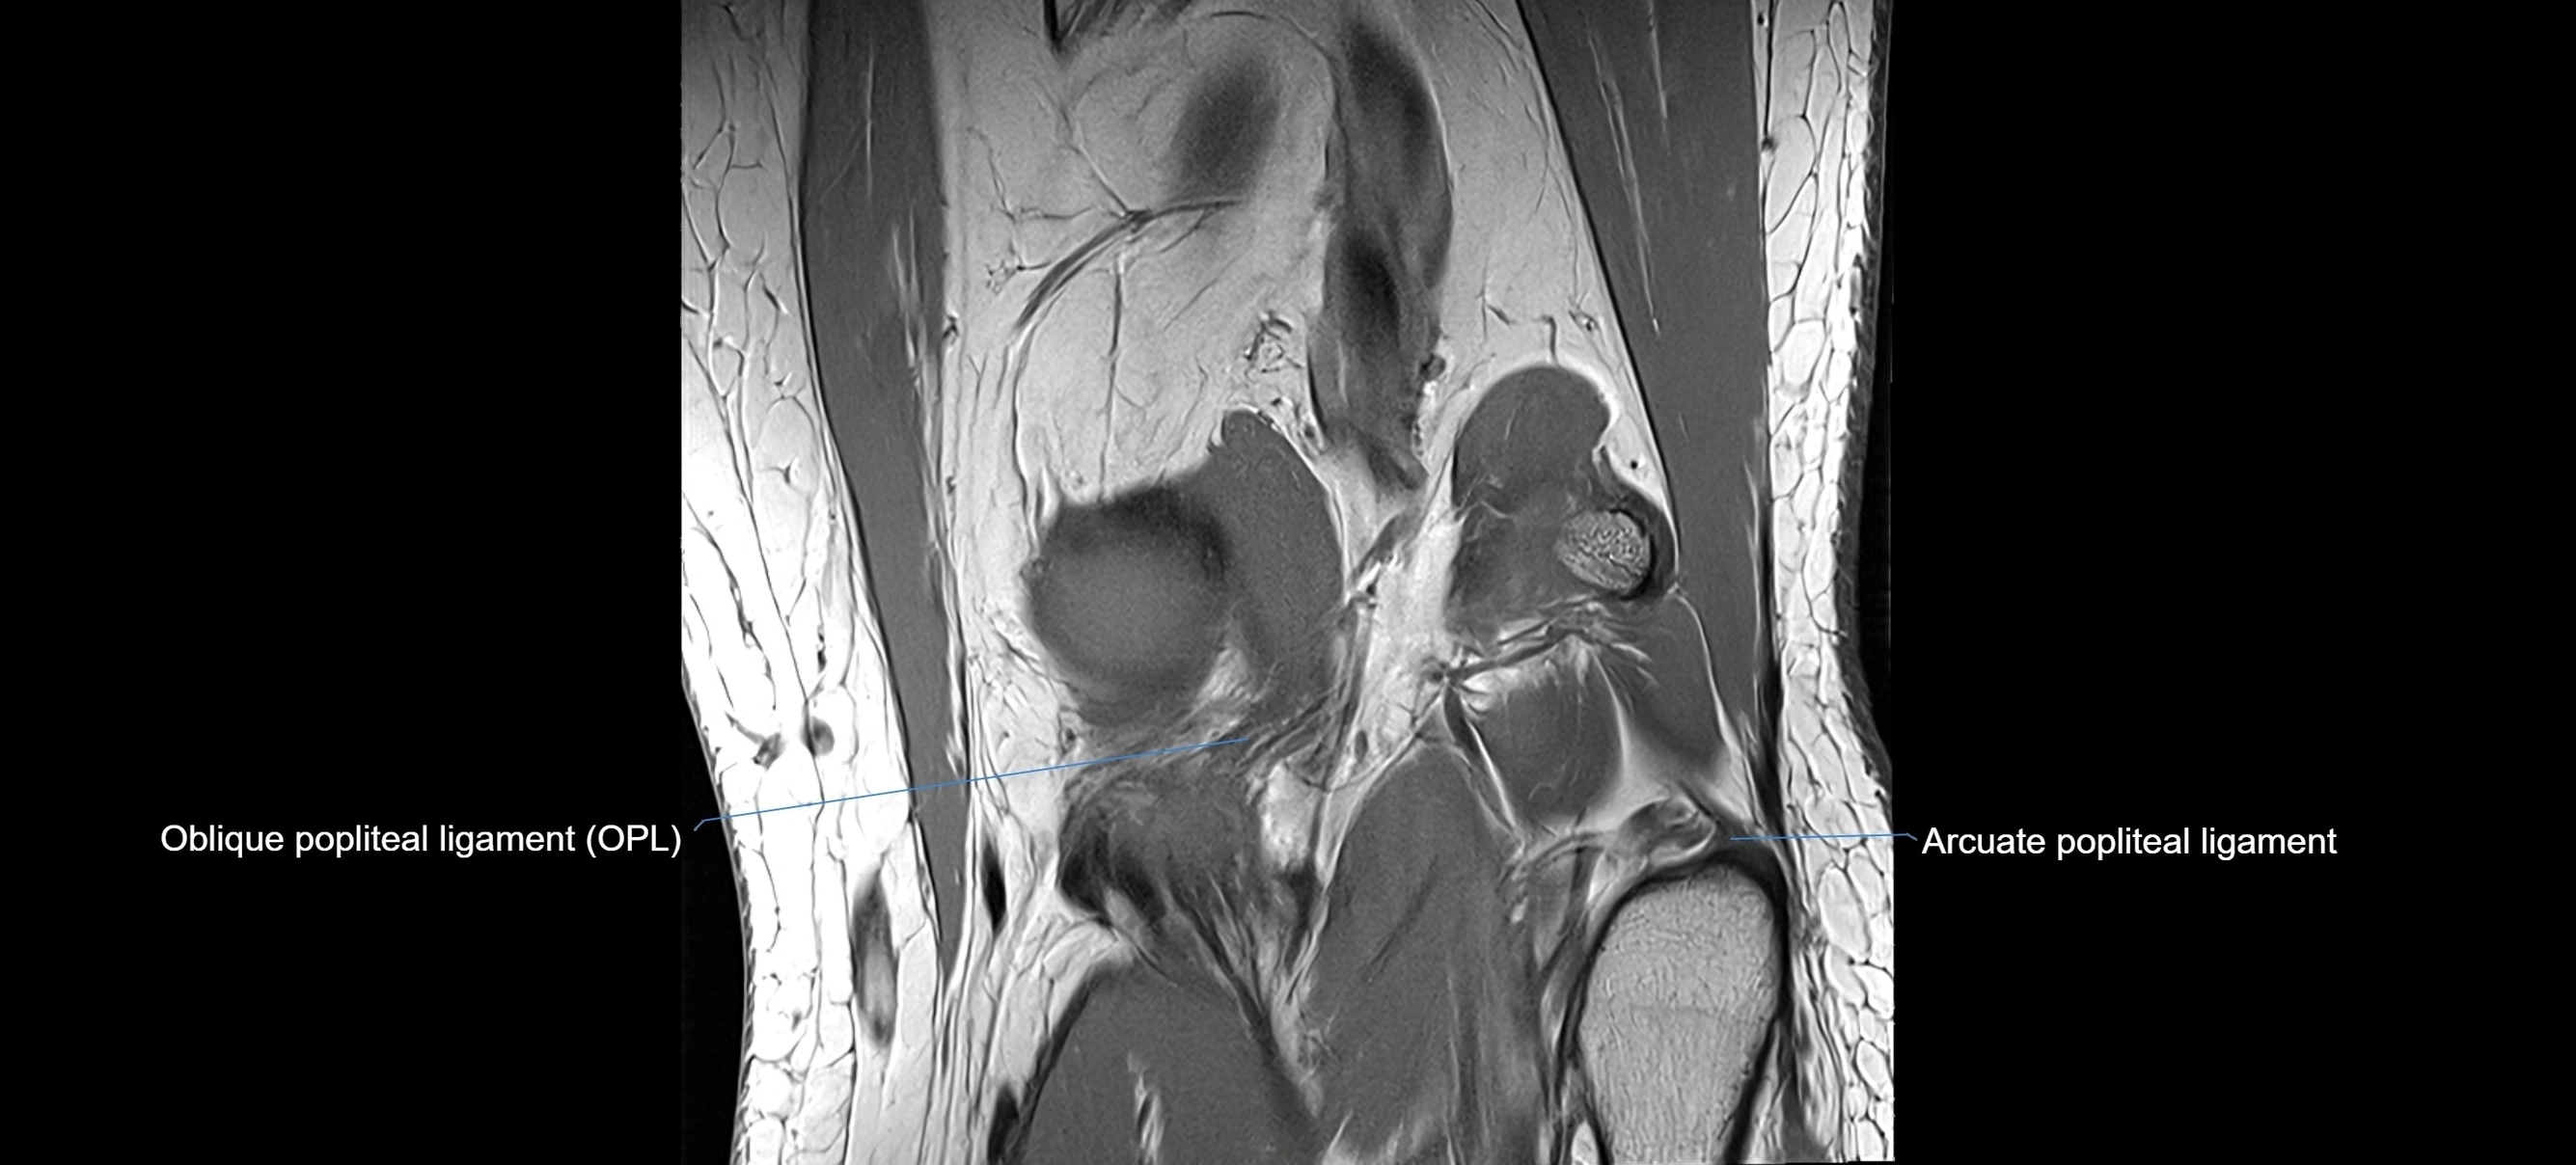

MRI images

image